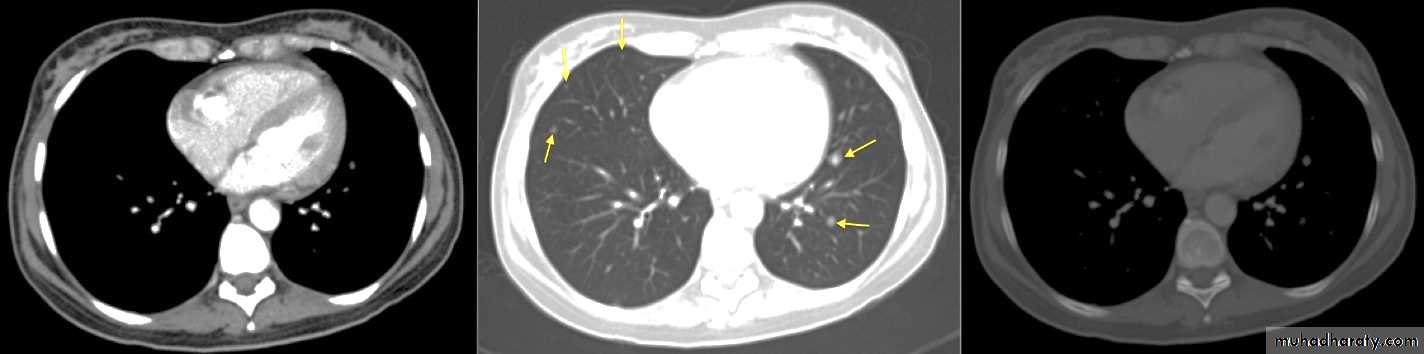

Grey scale window width and level

Mediastinal soft tissue w. Lung window Bone window

Intravenous iodinated contrast material USES in CT:• Differentiation of normal blood vessels from abnormal masses, e.g. hilar vessels vs. LN.